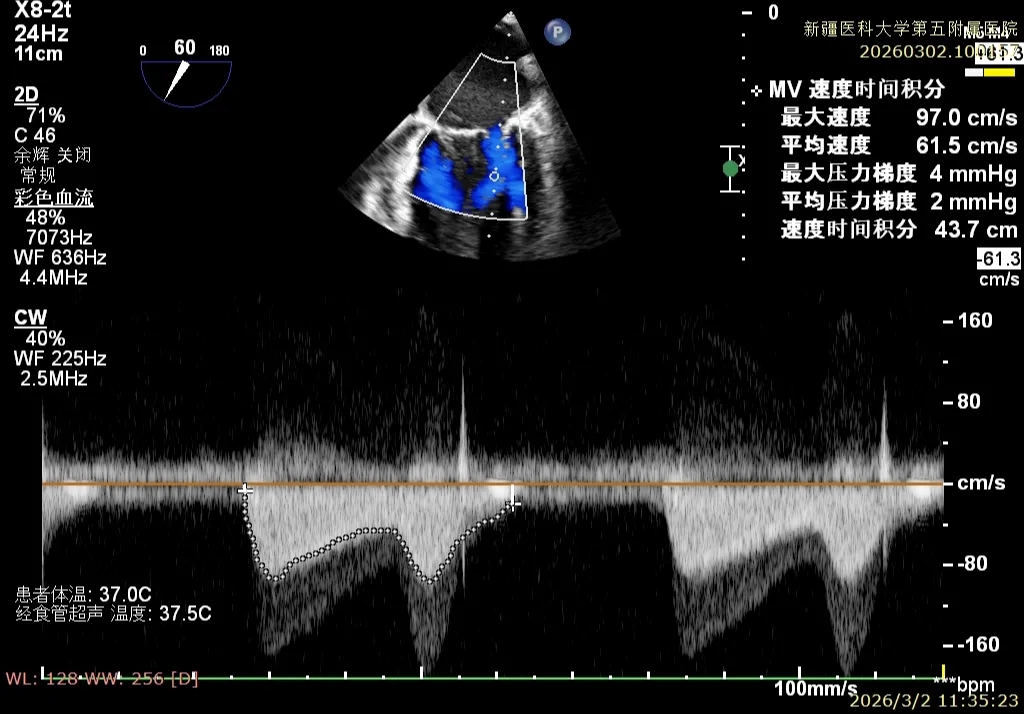

患者为房间隔缺损术后合并功能性二尖瓣反流(FMR),病变位于二尖瓣2区偏3区,因既往ASD修补史(可降解房间隔缺损封堵器),致房间隔穿刺区域存在瘢痕粘连、穿刺难度增加,于靠下靠后位置穿刺,避开房间隔缺损封堵伞,其余病变解剖结构相对简单;术前制定手术策略,拟使用1把XTR行二尖瓣修复,术中克服瘢痕粘连难点成功完成房间隔穿刺,穿刺点距二尖瓣瓣环平面3.1cm,将XTR‑CDS送入左心房,通过”A”旋钮旋转180度借高度,LVOT切面夹子严重Huge,使用”+”旋钮一键消除Huge,通过操控“M”旋钮将二尖瓣夹精准定位于2区正上方,完成弹道测试及Orientation调整后,于2区将夹子送入左心室,顺利捕捞并夹持瓣叶后缓慢闭合夹臂;TEE检查示二尖瓣反流充分降低至微量,二尖瓣双孔组织桥稳定,跨瓣压差2mmHg,肺静脉逆流明显改善,手术安全顺利结束。

术后平均跨瓣压差2mmHg